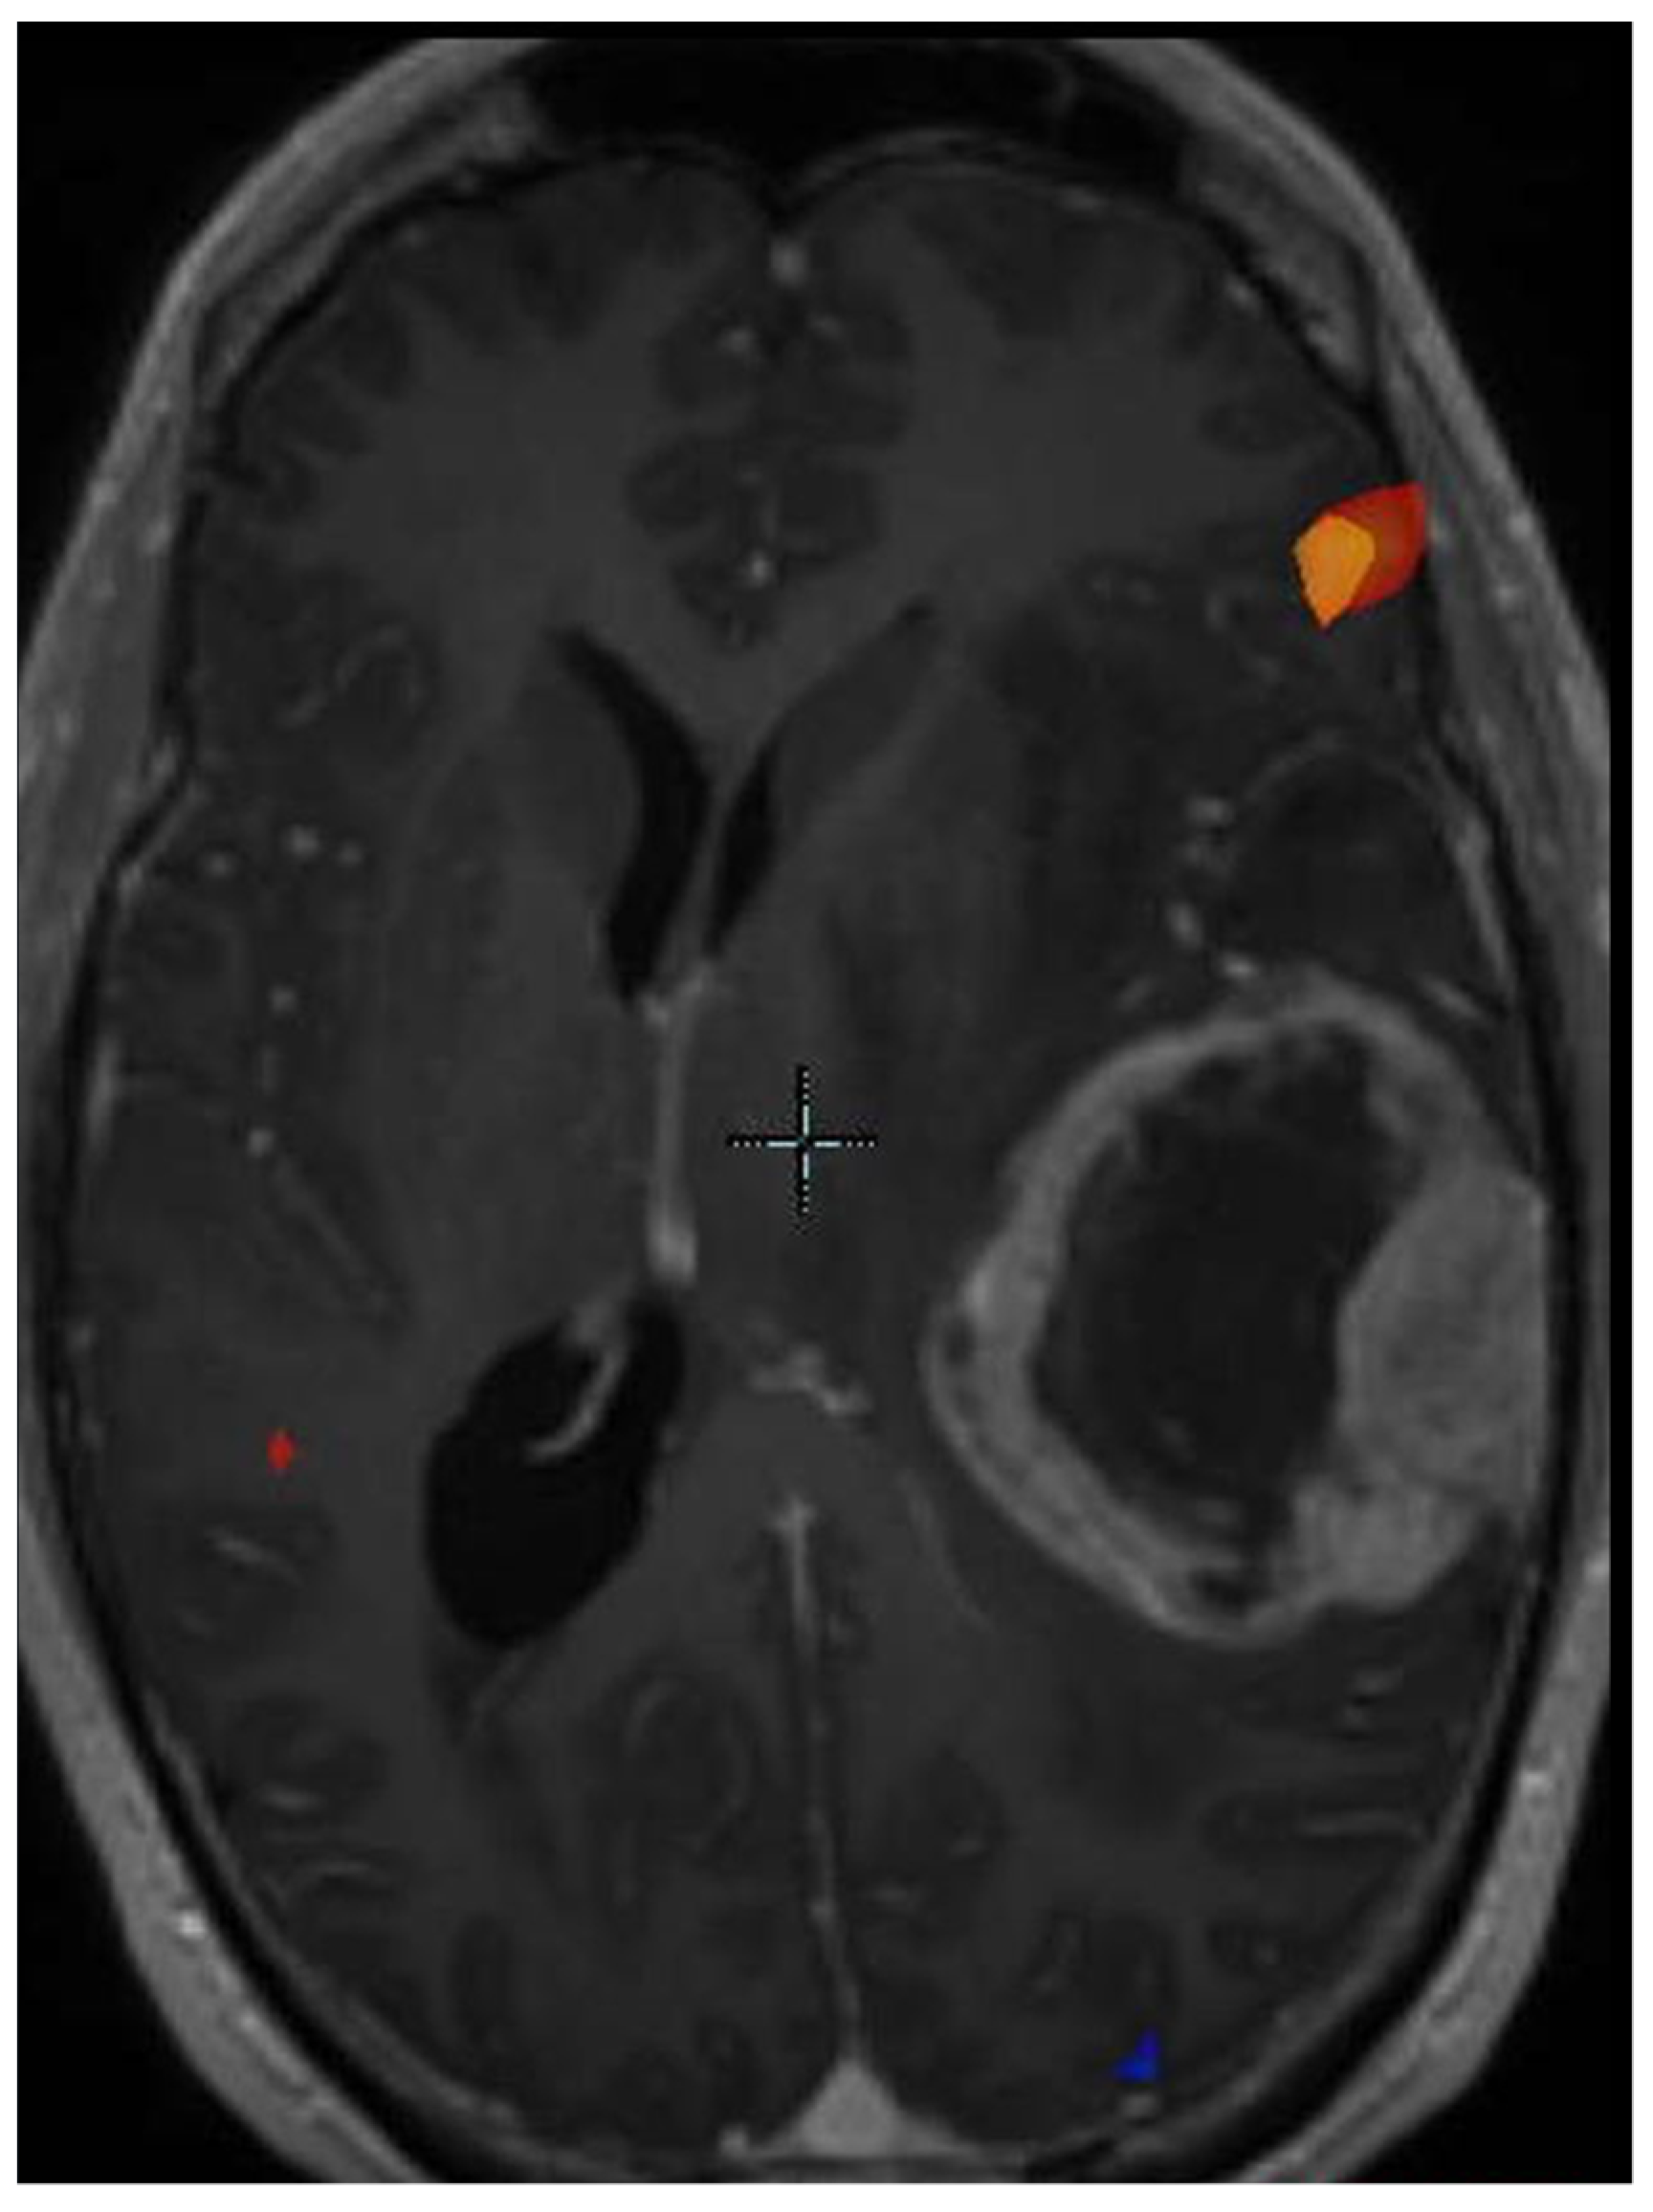

8. Progression of Disease versus Treatment Effect

- Gahramanov, S.; Raslan, A.M.; Muldoon, L.L.; Hamilton, B.E.; Rooney, W.D.; Varallyay, C.G.; Njus, J.M.; Haluska, M.; Neuwelt, E.A. Potential for differentiation of pseudoprogression from true tumor progression with dynamic susceptibility-weighted contrast-enhanced magnetic resonance imaging using ferumoxytol vs. gadoteridol: A pilot study. Int. J. Radiat. Oncol. Biol. Phys. 2011, 79, 514–523. [Google Scholar] [CrossRef] [PubMed]

- Henriksen, O.M.; Del Mar Alvarez-Torres, M.; Figueiredo, P.; Hangel, G.; Keil, V.C.; Nechifor, R.E.; Riemer, F.; Schmainda, K.M.; Warnert, E.A.H.; Wiegers, E.C.; et al. High-Grade Glioma Treatment Response Monitoring Biomarkers: A Position Statement on the Evidence Supporting the Use of Advanced MRI Techniques in the Clinic, and the Latest Bench-to-Bedside Developments. Part 1: Perfusion and Diffusion Techniques. Front. Oncol. 2022, 12, 810263. [Google Scholar] [CrossRef] [PubMed]

- Jones, K.K.; Maziero, D.; Ford, J.C.; Stoyanova, R.; Goryawala, M.; Diwanji, T.; Mellon, E.A. MRI-guided radiotherapy identifies early pseudoprogression of glioblastoma. Res. Sq. 2020. [Google Scholar] [CrossRef]